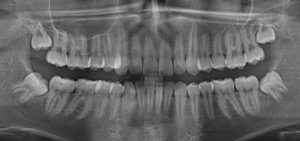

Неделю назад обнаружила маленькую межзубную щель на переднем коренном резце. Через несколько дней зуб немного зашатался. Он до сих пор шатается, но не очень значительно. И воспален межзубной сосочек.

Какие могут быть последствия? Может ли зуб увеличить шаткость? Или же его не трогать и он сам окрепнет?

Сам он конечно не окрепнет, я подозреваю, что у вас десневой карман, отсюда и воспаления сосочка и подвижность зуба. Необходимо обратиться к врачу на лечение. Не тяните, это в ваших интересах.